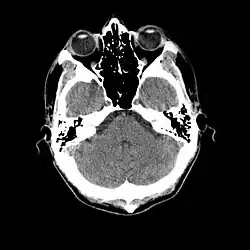

- Cranial computed tomography (CT, invented 1972) proved to be an excellent tool for diagnosing cerebral neoplasms in children, including those found in tuberous sclerosis.[46]

- MR was judged superior to CT imaging for both sensitivity and specificity. In a study of fifteen patients, it identified subependymal nodules projecting into the lateral ventricles in twelve patients, distortion of the normal cortical architecture in ten patients (corresponding to cortical tubers), dilated ventricles in five patients, and distinguished a known astrocytoma from benign subependymal nodules in one patient.[53]

- 1987

- MR imaging was found to be capable of predicting the clinical severity of the disease (epilepsy and developmental delay). A study of 25 patients found a correlation with the number of cortical tubers identified. In contrast, CT was not a useful predictor, but was superior at identifying calcified lesions.[54]